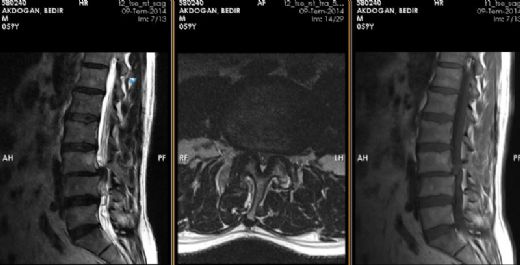

Bel Fıtığı ve Platin Takılması: Genel BilgilerBel fıtığı, omurganın aşağı kısmında yer alan disklerin (intervertebral disklerin) yıpranması sonucunda oluşan bir rahatsızlıktır. Bu durum, diskin içindeki jel benzeri maddelerin dışarı çıkması ve sinirlere baskı yapmasıyla karakterizedir. Bel fıtığı, sırt ağrısı, bacaklarda uyuşma, güçsüzlük ve hareket kısıtlılığı gibi belirtilerle kendini gösterir. Platin Takılması: Neden ve Nasıl Uygulanır? Bel fıtığı tedavisinde, cerrahi müdahaleler gerekebilir. Bu tür durumlarda, omurga stabilitesini sağlamak amacıyla platin (metal veya biyomateryal) takılması tercih edilebilir. Platin, omurga yapılarını bir arada tutarak iyileşme sürecine destek olur. Platin Takılmasının Zararları Platin takılmasının bazı potansiyel zararları ve komplikasyonları şunlardır: